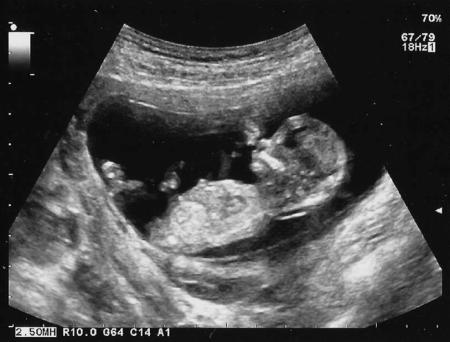

At my 20 week scan which happened to be on mine and my fiancés anniversary we were reassured that everything was perfect, heart was fine, kidneys, spine, they even showed us that her lip was formed perfectly. The clot was still there but it didn’t seem to be affecting anything so no one seemed that worried. She kept her legs crossed though keeping us guessing about her gender! It was the most perfect anniversary present for the both of us. I started to relax thinking that the second half of my pregnancy would be ok, the risky part was over, she was ok and perfectly formed, she just needed to grow now, after all, in 4 weeks she would be viable!

The next morning mum made me phone the doctors seeing If they could book me in with the midwife but they were booked up, so I phoned the midwife line and they told me that people often stopped feeling their babies as they moved around and that she didn’t approve of people using their own Dopplers as they weren’t trained and didn’t know how to use them but if I was really worried there was a midwife clinic. I was completely put off by her attitude, almost as if I didn’t know what I was talking about and was just being a stupid hypochondriac. Mum forced me to go to the clinic and when the midwife there couldn’t find her heartbeat she sent me straight to the hospital for an emergency scan. I can remember every detail of that afternoon, I called my fiancé telling him to get to the hospital NOW! Luckily it was his day off, and I lay there while the doctor scanned my tummy, a sick copy of the scan less than a week earlier filled with positive comments and lots of movement on the screen, I watched the screen this time waiting for any sign of movement, but I didn’t see any, eventually when he looked at me I knew exactly what he was going to say, there was no heartbeat, my baby had died about three days earlier. Grief crashed around me and a gutteral scream escaped my lips, I just sobbed, I didn’t have a clue what to do.